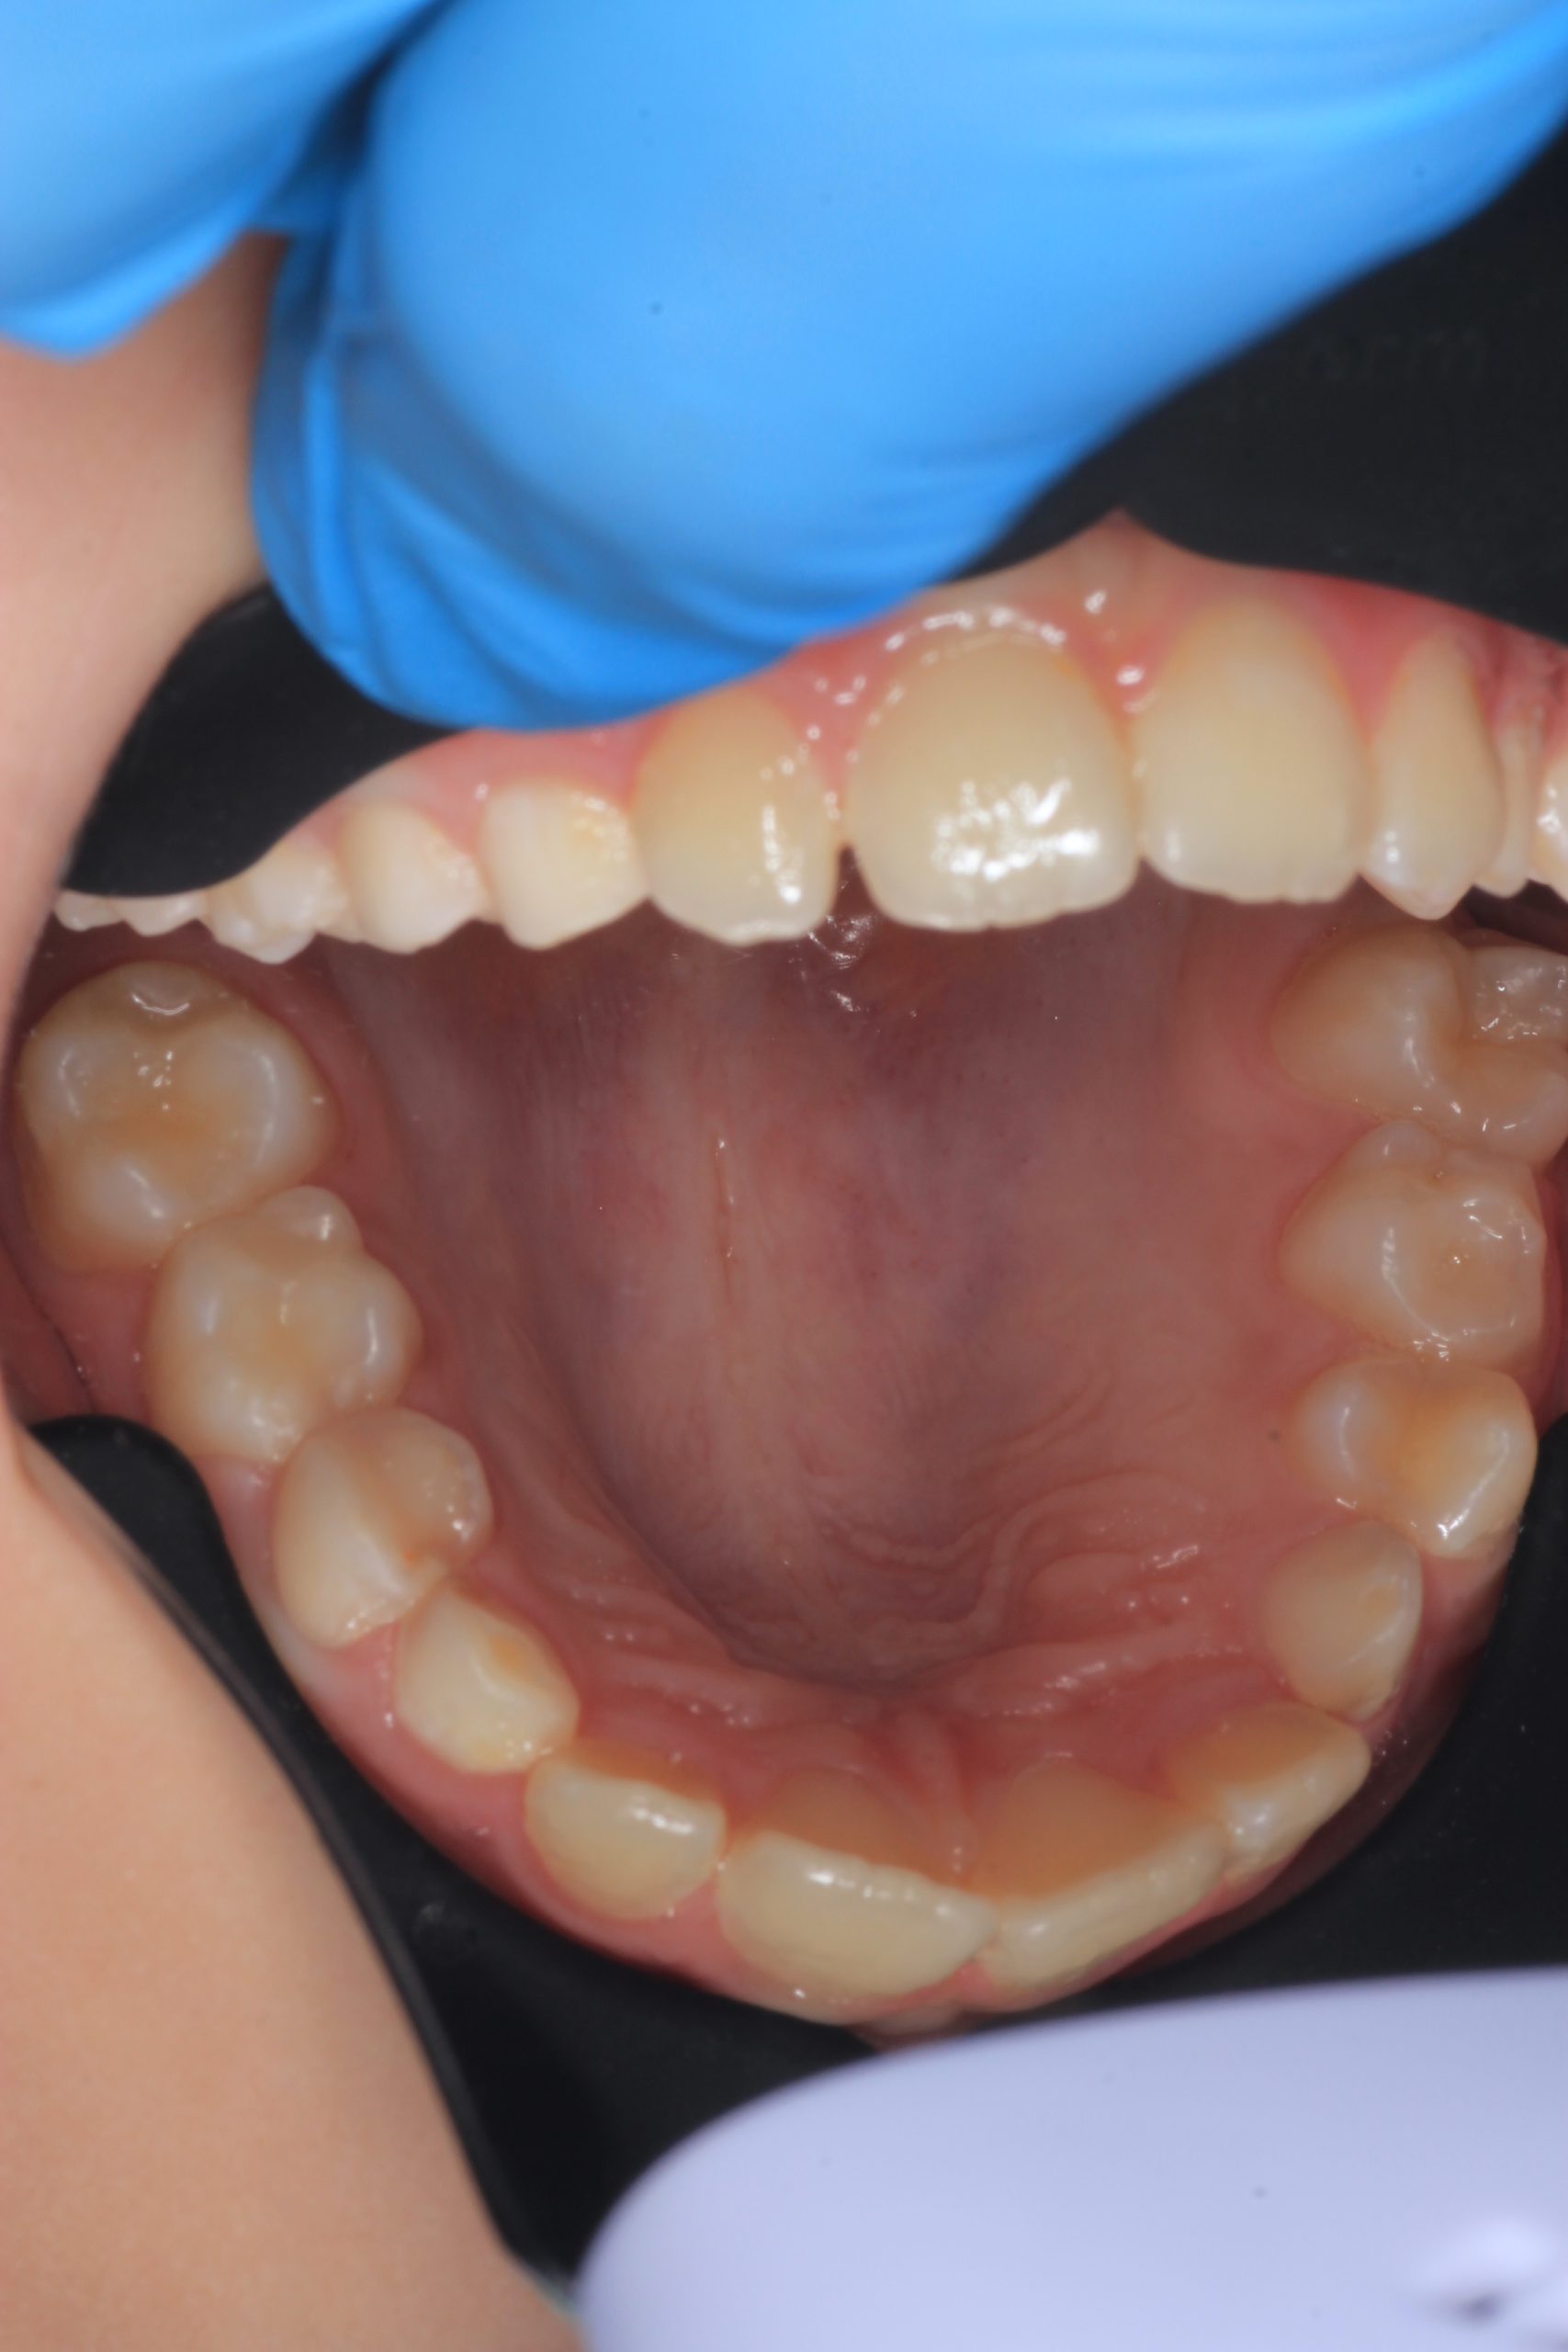

Together with your child, we practice brushing techniques, correct mistakes, and provide personalized recommendations. We advise whether to use manual or electric brushes, floss, interdental brushes, or remineralizing gels. - Plaque Removal with AIRFLOW Prophylaxis Master (EMS, Switzerland)

From age 4–5 and up, we perform full GBT cleaning using an ultra-fine erythritol powder to clean even hard-to-reach areas gently and safely. It does not damage enamel and is ideal even around braces — no need to remove brackets or wires. - Tartar Removal (If Needed)